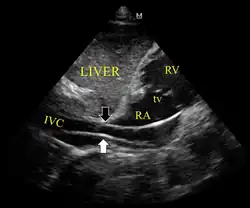

Ultrassonografia mostrando o dispositivo no ventrículo direito

Dispositivo passando de forma inadequada para a veia cava inferior

O dispositivo de estimulação também pode ser avançado através da veia sob orientação de eletrocardiografia (ECG) ou ultrassom [1][5]. Antes de puxar o dispositivo para trás, certifique-se de que o balão esteja vazio[2].